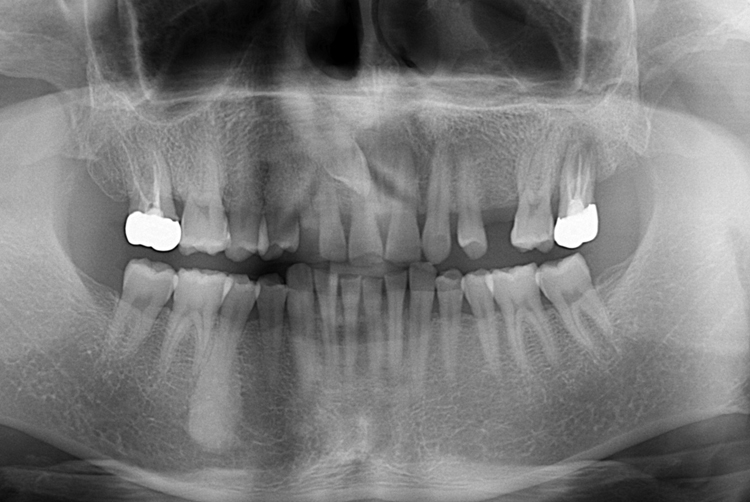

[임플란트] 어금니 임플란트

치료전 : 2019-07-10